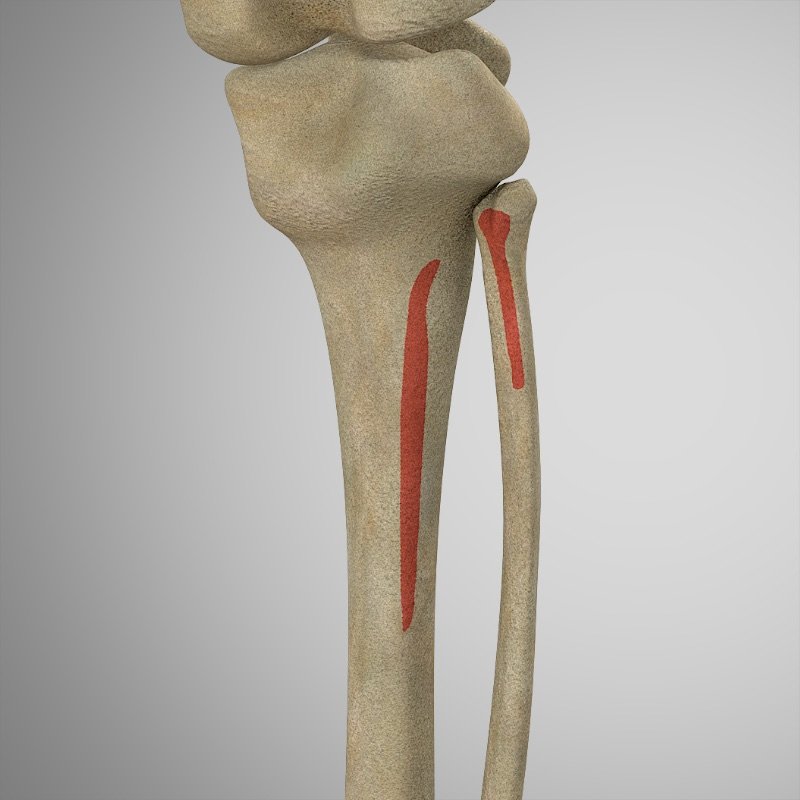

ORIGEN

- Línea del sóleo en la Tibia

- Cabeza del peroné